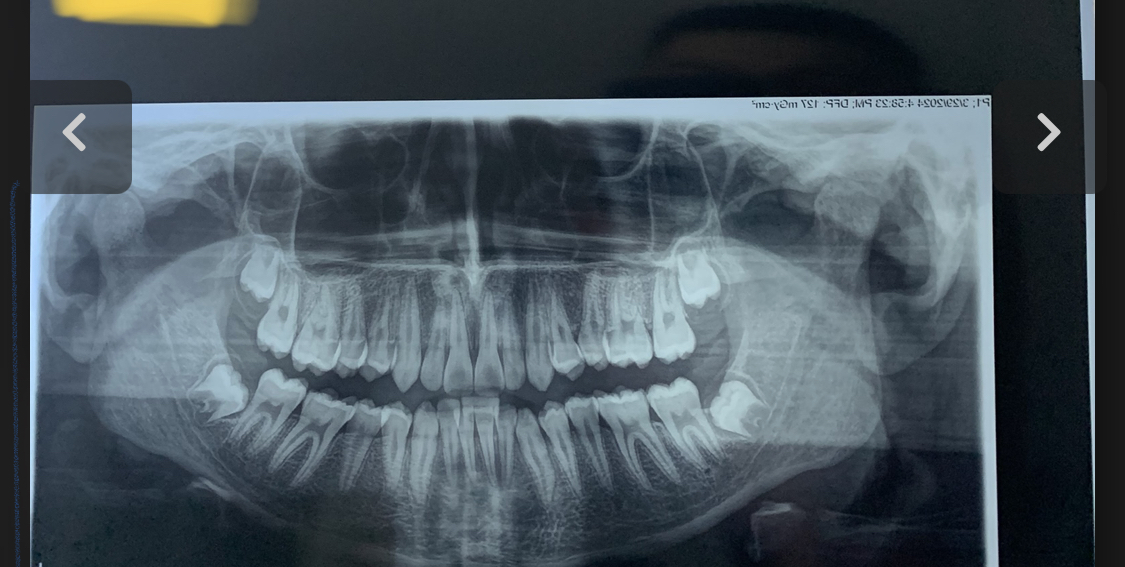

The right side is the side i chewed gum a lot u clearly can see the difference

Ok see the left side of my jaw does my genetics only apply only in one side ?gonian shape, masseter insertions, how much your gonians flare and so on